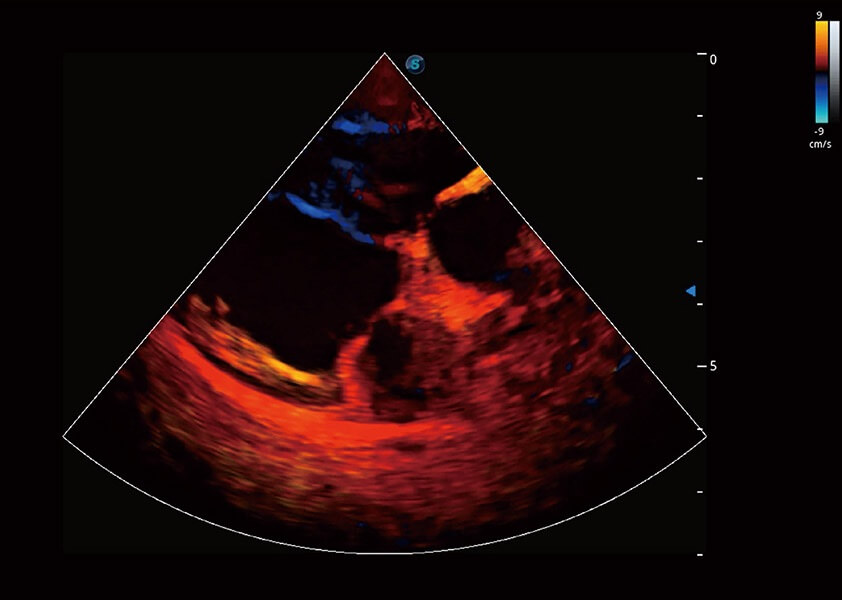

• TDI 组织多普勒成像

实时用颜色表示心肌组织运动,观察和定量组织的运动情况,对快速检测与评估心肌的灌注和活性、电传导及心肌收缩和舒张功能等均能提供重要的诊断信息。

优异的基础图像

(犬)心脏组织多普勒